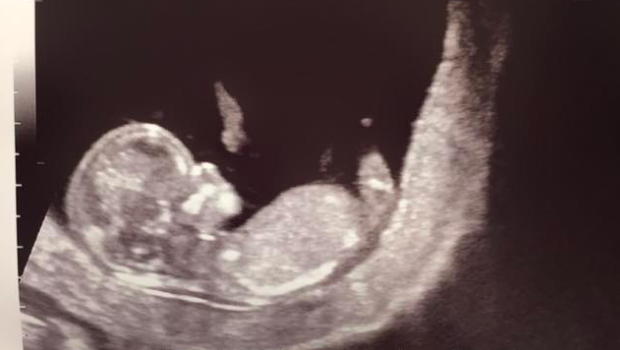

A few months ago Jaime and I got the news I never thought I would.

After years of thinking that chemo may have stripped me of my ability to have children, this little guy suddenly appeared. I still can’t quite believe it. My thirties started off as a nightmare but now they feel like a dream. I feel like I am the most grateful person in the world.

This little miracle will be arriving later on this summer. My greatest adventure yet!